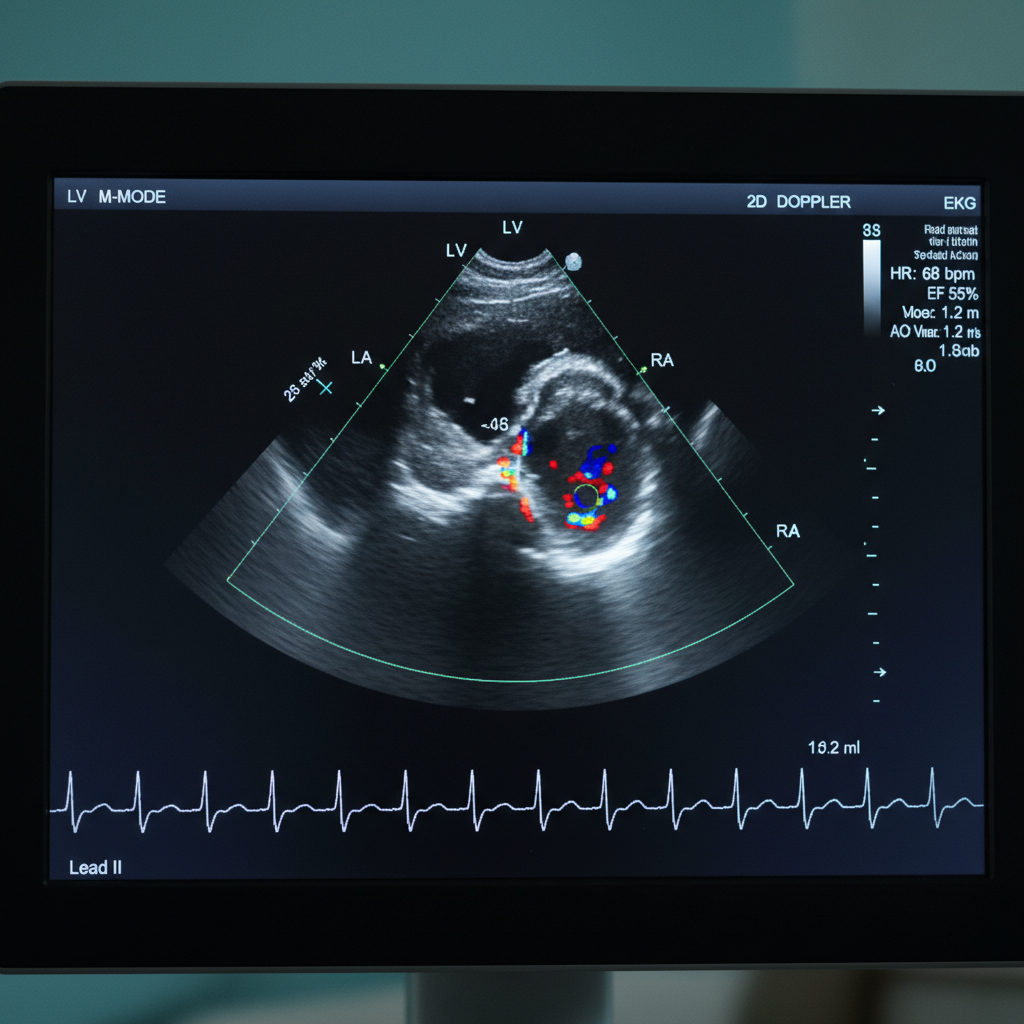

- Định nghĩa: Siêu âm tim (echocardiography) là một kỹ thuật sử dụng sóng siêu âm để tạo ra hình ảnh về cấu trúc và chức năng của tim.

- Chức năng: Siêu âm tim giúp đánh giá khả năng co bóp của tim, kích thước và hình dạng của các buồng tim, và phát hiện các dị tật tim bẩm sinh.

- Các loại: Có nhiều loại siêu âm tim khác nhau như 2D, 3D, 4D, và Doppler, cung cấp thông tin phong phú về tim.